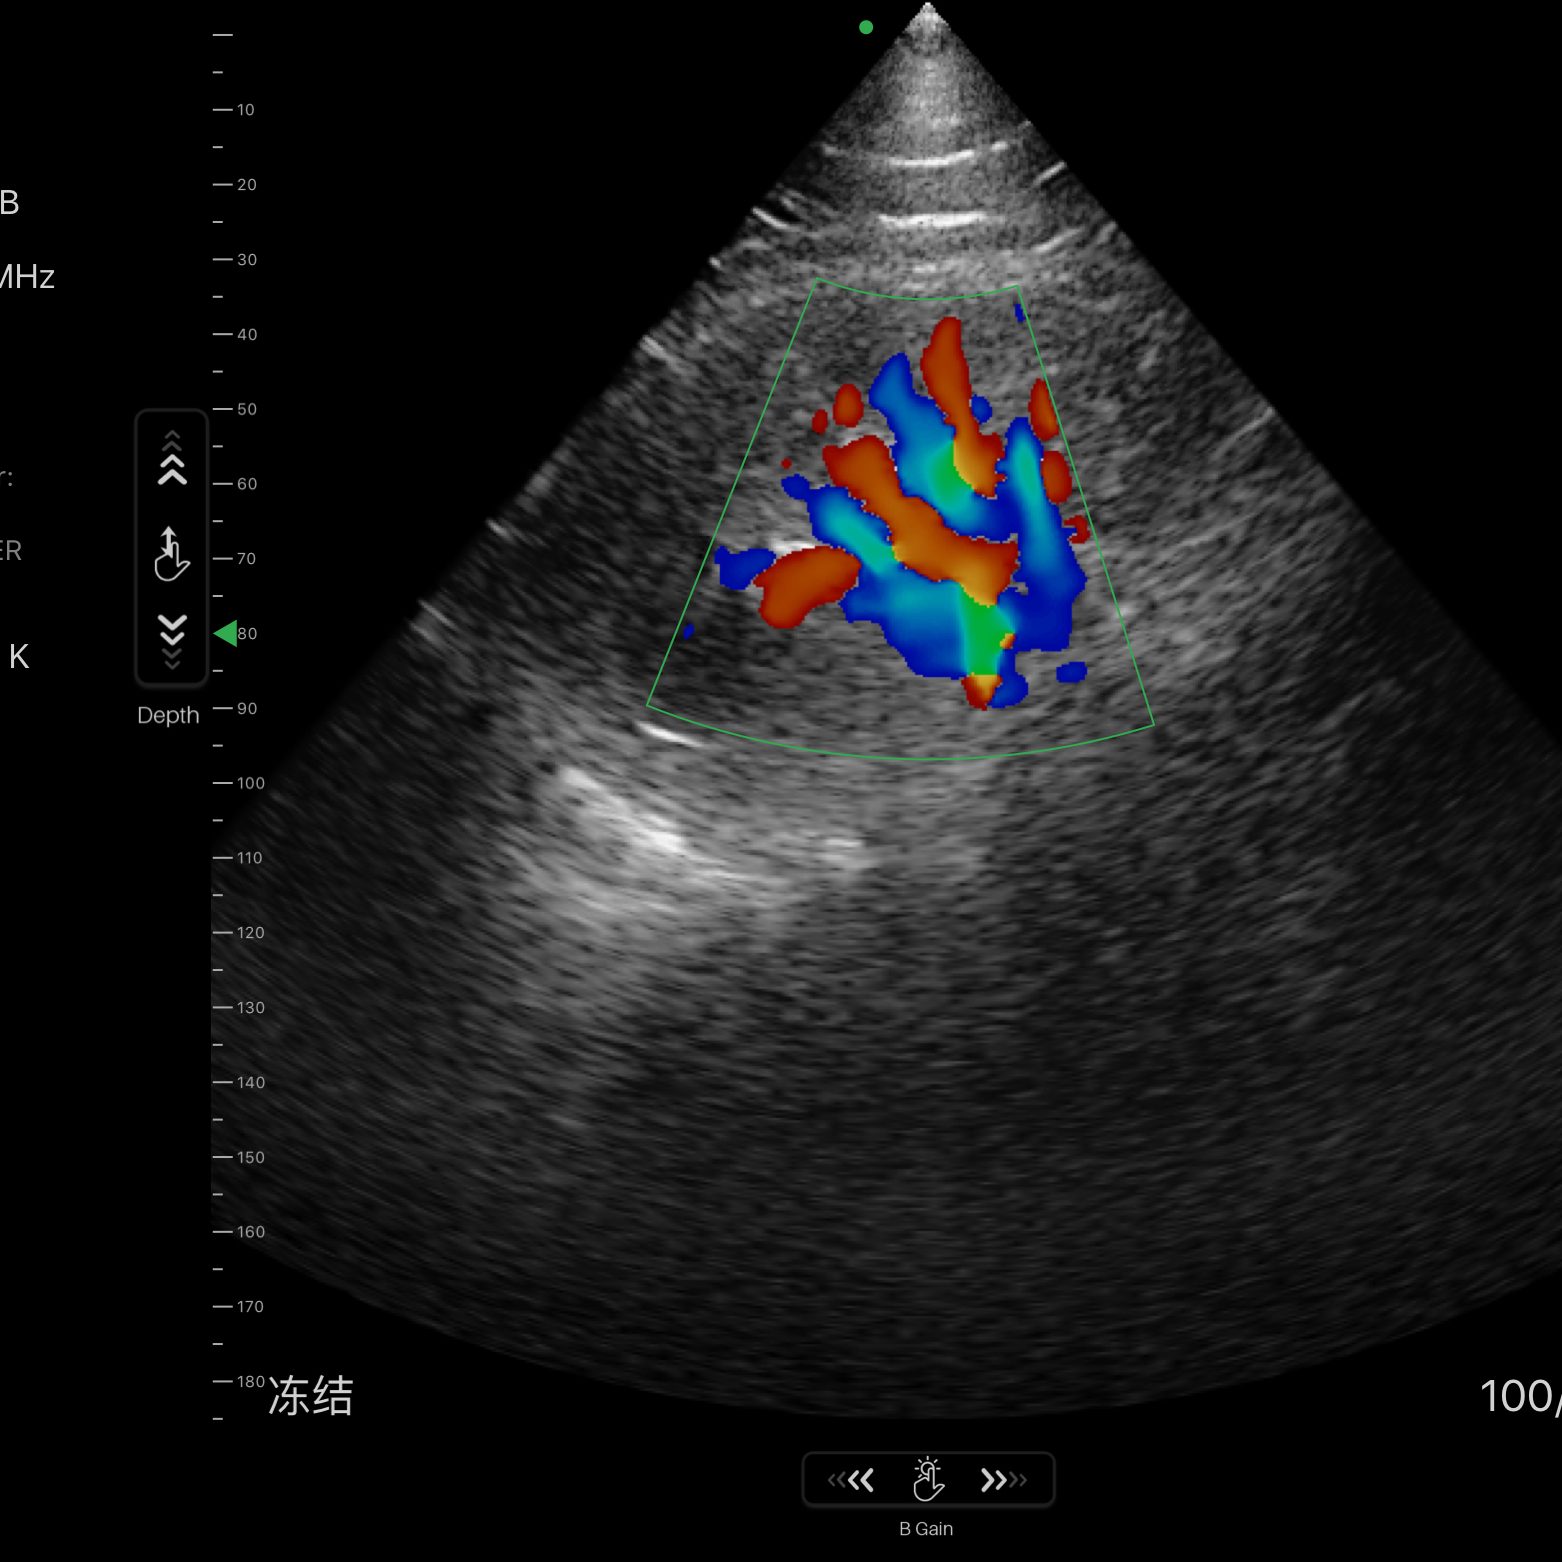

| Modo de escaneo | B, B/M, Color, PW |

Modos de escaneo: B, B/M, Color, PW

Exámenes básicos y control de flujo cardíaco o vascular en entornos clínicos y extrahospitalarios.